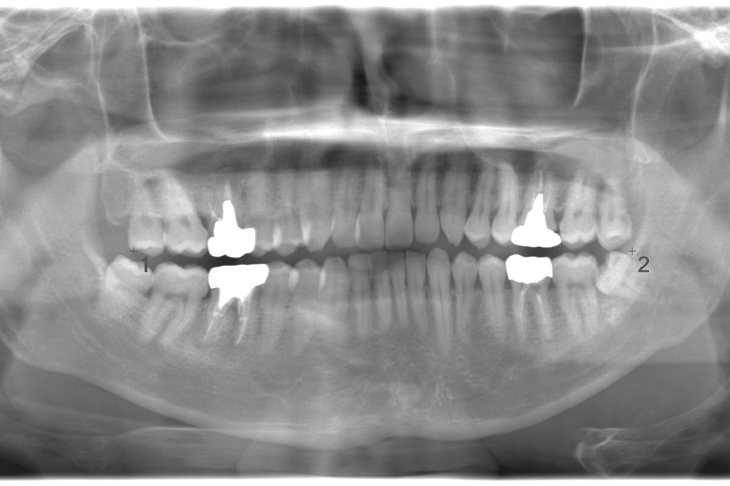

CASE 11

基本情報

| 年齢・性別 | 33歳・男性 |

|---|---|

| 主訴 | 左上下親知らず抜きたい |

| 抜歯期間 | 30分 |

| 抜歯費用 | 約2,500円(保険内) 別途CT撮影で3,000円 (2022年7月現在) |

| 抜歯内容 | 左上下の親知らず抜歯 |

| 治療方針 |

初めに右下の奥歯が痛いとのことでご来院されました。 右下の親知らずと7番目の歯がカリエスになっていたため、まずは右下の親知らず抜歯と7番目の感染根管治療を行いました。左上下の親知らずもカリエスになっているため、今回抜歯を行いました。 |